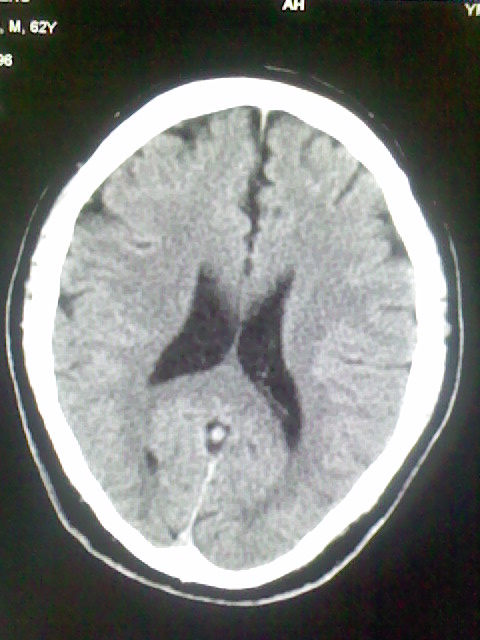

标题: CT15555:头痛 10余日 来诊大家帮忙看看 [打印本页]

标题: CT15555:头痛 10余日 来诊大家帮忙看看

脑萎缩

脑沟、裂增宽,提法脑萎缩,建议mt检查。

脑萎缩,以小脑为著。

脑沟、裂增宽,提示脑萎缩

老年脑

支持轻度脑萎缩。